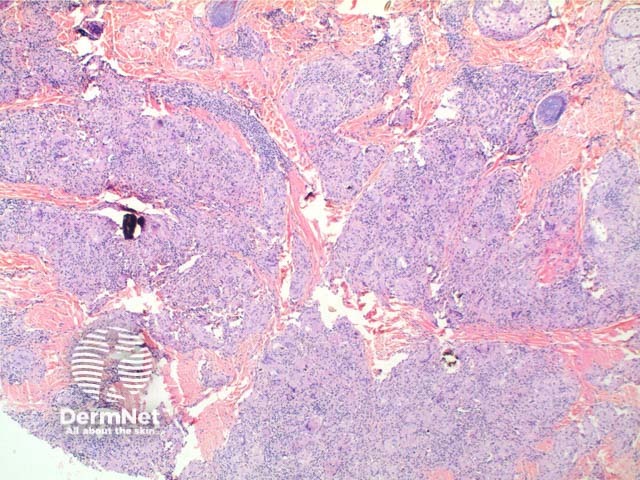

Scanning power view of sarcoidosis shows a granulomatous reaction pattern (Figure 1) characterised by multiple discrete predominantly epithelioid granulomas (Figures 2 and 3). Necrosis is uncommonly seen. The granulomas are typically ‘naked’ with few surrounding lymphocytes and a rim of mild dermal fibrosis.

Foreign bodies are not uncommonly seen within sarcoidal granulomas (Figures 2, 3 and 4) and are more common within sites prone to trauma. The presence of birefringent material therefore does not exclude sarcoidosis. Foreign material may serve as a nidus for sarcoidal granuloma formation in some cases.

Figure 2